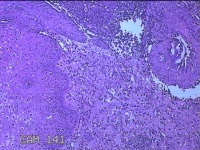

宫颈2点、3点、9点组织

性别

女

年龄

38岁

临床诊断

人乳头瘤病毒感染

一般病史

宫颈其他HPV12阳性

标本名称

大体所见

1.“宫颈2点组织”:灰白粉红色组织0.8x0.5x0.2cm一块。 2.“宫颈3点组织”:灰白粉红色组织0.7x0.5x0.2cm一块。 3.“宫颈9点组织”:灰白粉红色组织0.7x0.5x0.2cm一块。